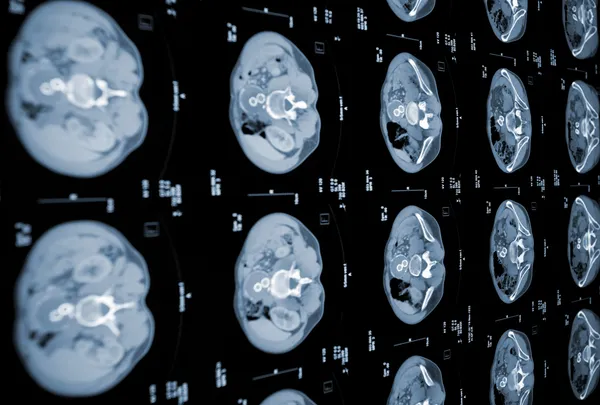

Kalın bağırsak, su ve atık maddeleri içine alarak dışkıya dönüştüren tüp benzeri bir organdır. Hastalık genellikle, kalın bağırsağın duvarında polip adı verilen iyi huylu yumrular şeklinde başlıyor. Polipler küçük olduğunda, semptomlara neden olma olasılığı düşük oluyor. Bu nedenle, poliplerin erken dönemde kansere dönüşmeden tespit edilmesi için düzenli olarak taramadan geçmek gerekiyor.

Polipler büyüyerek kansere dönüşmeye başladığında, kalın bağırsakta hasar meydana geliyor.